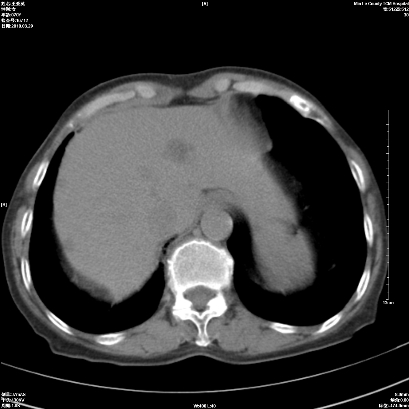

1 右肺门占位伴上叶不张 2 有肺多发感染 3 肝脏转移? 建议增强

1、右侧中央型肺癌伴右肺上叶不张建议支气管镜检   2、右肺中叶及下叶陈旧性病灶   3、肝内多发低密度影,肝内多发转移不除外,建议ct增强!

肝脏多发占位建议增强检查

1)考虑右肺中央型肺癌伴右肺上叶肺不张,右肺门淋巴结转移;建议行支纤维镜检查。2)右肺中叶、下叶及左肺上叶舌段感染性病变。3)肝内多发低密度影,不排除转移瘤可能;建议行ct增强扫描检查。

作者: yangyang2000    时间: 2010-3-31 04:52